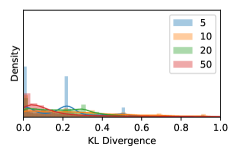

5.1 Distribution of Uncertainty Scores

Distribution of Uncertainty Scores Across Different Severity Levels As explained in Section 3, each uncertainty metric essentially defines an order/ranking among the data points. We conducted an analysis to better understand what data will be assigned high uncertainty under a particular uncertainty metric . Picking out the highest ranked data points (), we calculated the ratio of data points from each SL. Figure 4 summarizes the results as box plots for the Kaggle-DR and the Messidor-2 datasets; additional detailed statistics can be found in Table S.1 in the supplementary materials. From the plot and table, SL1 & SL2 examples account for a higher proportion among the top-ranked uncertain examples across the three ensemble methods. This finding matches our intuition that incipient disease examples (SL1 & SL2) are more likely to be considered uncertain by ensemble methods due to their ambiguity.

Uncertainty Scores on Out-of-Distribution Datasets As an additional experiment, we also tested the performance of the ensemble models on o.o.d. data inputs, which is a classic application of prediction uncertainties [1]. For this task, we produced distribution plots similar to those in Figure 4 for the previous experiment in our supplementary materials. The visualizations for the two o.o.d. image datasets can be found in Figure S.5 for ImageNet and in Figure S.6 for CIFAR-10. The results showed that the majority of o.o.d. data received higher uncertainty scores than in-distribution data for all three ensemble methods, suggesting that these ensemble methods would indeed perform well on o.o.d. detection tasks.

Comparing the three ensemble methods in Figure 4, the stacking ensemble method has the highest ratios of SL1 & SL2 data among the high-uncertainty examples it identified under both mean and var. TTA showed slightly better performance than MC-dropout but still falls behind the stacking ensemble method. Considering the fact that SL0 examples accounted for the majority of the dataset, the stacking ensemble method was much more precise (specific) in selecting truly ambiguous data points that were difficult to classify. From Figure 3, we can also see that the stacking ensemble method greatly outperformed the other two methods in finding false negatives under both mean and var uncertainty metrics.

In contrast, the MC-dropout method showed the worst overall performance among the three, as it can be seen from the high ratios of SL0 examples among the uncertain negatives in Figure 4. The histograms in Figure 2 provides another perspective to look into the phenomenon, where a decent proportion of MC-dropout model’s predictions on SL0 inputs entailed low confidence (far from 0 or 1), which from another angle explained why MC-dropout was less specific in terms of lower FNP; many no-DR inputs (i.e. SL0) were erroneously assigned high uncertainty by MC-dropout models.

It is still an open question why the evaluated MC-dropout networks signaled relatively high uncertainty on SL0 & SL3 & SL4 data that are less likely to be ambiguous. We conjecture that much of the “uncertainty” indicated by disagreement among test-time dropout samples actually reflects the stochastic nature of dropout networks rather than the real decision uncertainty associated with the data. It is worth noting that the MC-dropout model we evaluated was not weak per se; they all achieved above Area Under Curve (AUC) scores on test sets. The weakness of individual test-time samples (which explains their low-confidence predictions on SL0 & SL3 & SL4) might have been hidden when they are aggregated into an ensemble—a well-known advantage of ensemble learning. Our results suggested that the uncertainty information given by implicit ensemble methods such as MC-dropout and TTA might not be as reliable as that from explicit ensemble approaches (e.g., stacking ensembles). Similar findings on MC-dropout can be found in some previous papers [1].

As discussed in Section 5.1 and Section 5.3 in the main paper, the mean metric and the stacking ensemble will have better performance in the precision (specificity) on the ambiguous data. Here, more detailed results are shown in Figures S.3 & S.6 and Table S.1. Figures S.3 & S.4 show the histograms of the uncertainty score for Kaggle-DR and Messidor-2 datasets that are the in-distribution (i.d.) dataset in our experiment and FigureS.5 & S.6 show the histograms for ImageNet and CIFAR-10 datasets, which is the o.o.d. datasets in our experiment. Each group of histograms contains results from the three evaluated ensemble methods (stacking ensemble, MC-dropout and TTA) and the three uncertainty metrics (mean, var and kl). Additional detailed results not displayed in Figure 4 can be found in Table S.1, which shows the proportion of the data of different SLs varies across different . For comparison, we also included in Table S.1 the results from single learners, and the proportions of data of different SLs (before any selection was made).